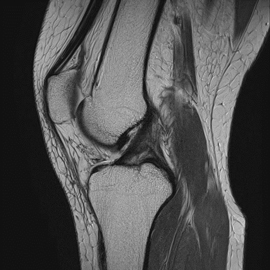

MRIはCTやX線撮影では分からない脳梗塞や、動脈瘤を可視化することができるため、脳卒中患者様においては重要な検査となっています。さらに、神経、靭帯、前立腺胆管、膵管などもよく分かるため、さまざまな診療科で需要は非常に高いです。